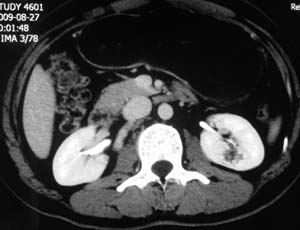

以下是引用子期在2010-3-19 20:47:00的发言:[br]血管畸形的ct增强应该有明显强化,本例并不相符合。本例双肾局部的略低密度影,累及肾盂,局部皮质明显变薄、内陷,增强扫描有轻度的强化,应考虑为炎性病变,患者为年轻男性,累及双肾的感染以结核较常见,可以没有明显的临床症状,尿中有时候也并不能查出什么;肾脓肿常有明显感染中毒症状,本例不符,另外一般的肾盂肾炎或肾小球肾炎通过小便就可确诊,其它还不能排除的是黄色肉芽肿性肾盂肾炎,然而单凭ct一般也很难鉴别。